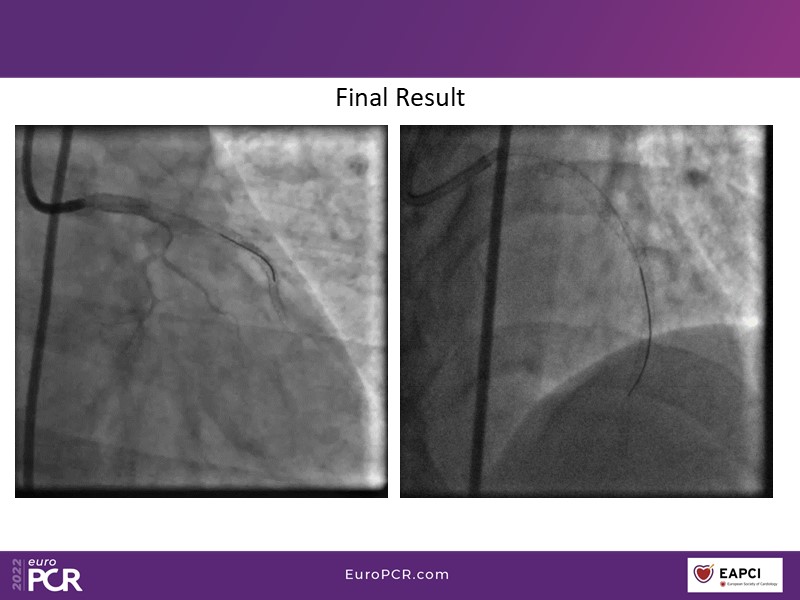

- To find out more about the application and mechanism of a sirolimus coated balloon for coronary artery disease treatment with case presentations in complex settings